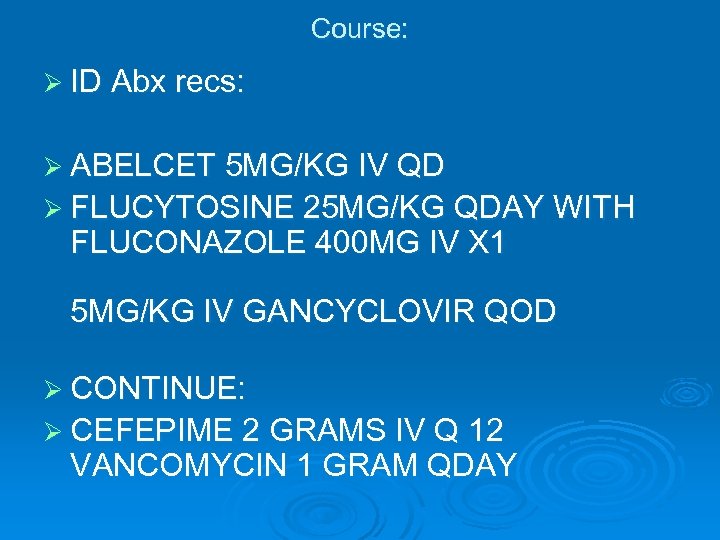

Course: Ø ID Abx recs: Ø ABELCET 5 MG/KG IV QD Ø FLUCYTOSINE 25 MG/KG QDAY WITH FLUCONAZOLE 400 MG IV X 1 5 MG/KG IV GANCYCLOVIR QOD Ø CONTINUE: Ø CEFEPIME 2 GRAMS IV Q 12 VANCOMYCIN 1 GRAM QDAY